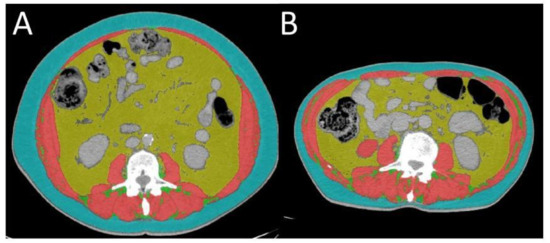

The CT images were acquired with similar acquisition parameters: tube voltage between 100 and 120 kVp, automatic tube current, soft tissue reconstruction algorithm, a 512 × 512 matrix, and a slice thickness of 5 mm. From these acquisitions, a single CT image localized at the third lumbar vertebral body (L3), depicting both the transverse processes, was selected by an experienced radiologist. The image was processed with ABACS software (version 2.0, Voronoi Health Analytics, Vancouver, BC, Canada) that, in a fully automated fashion, segmented and determined the cross-sectional surfaces of skeletal muscles (SKM, including paraspinal muscles, abdominal wall muscles, and the psoas), subcutaneous adipose tissue (SAT, including intramuscular fat tissue), and visceral adipose tissue (VAT) (Figure 3) [33]. All the segmentations and the measurements were reviewed, corrected when necessary, and validated by the radiologist.

Figure 3. Evaluation of body composition. An axial CT image segmented into the skeletal muscle area (SKM in red), visceral adipose tissue area (VAT in yellow) and subcutaneous adipose tissue area (SAT in green). Total adipose tissue area (TAT) is identified from VAT + SAT. (A) and (B) differ from body composition.